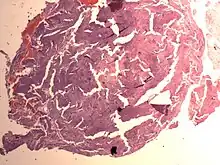

Endometrial Stromal Nodule

An endometrial stromal nodule is a noncancerous tumor of the uterus.[2]

It is a subtype of endometrial stromal tumor belonging to the mesenchymal tumors of the main body of the uterus.[1] The appearance of the cells is identical to normal endometrial stromal cells.[1] This can only be differentiated from low-grade endometrial stromal sarcoma by confirming lack of infiltration.